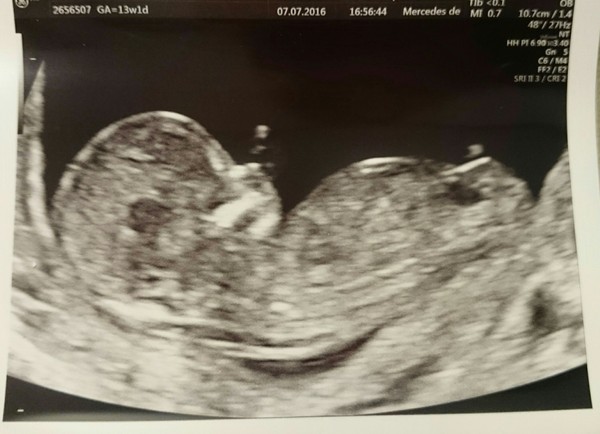

Ni4444 · 13/07/2016 21:31

Week 14 is great!! I feel fabulous!! Actually I just feel normal but after almost 10 weeks of daily baby hangover I forgot how good normal feels!!😀

Hey Stark! Thanks for the heads-up on the name change! That was a great scan photo! We had our first NHS one last week....so detailed!! Saw the different hemispheres of the brain, the spine, even counted fingers!!😀

Hi ni!!! Beautiful scan! Grin hopefully you continue to feel normal.

Ni long time no see Grin lovely scan photo Smile

Lovely scan Ni.

Welcome, Ni! So lovely to see you here, and glad to hear everything is going well!

Great scan and nice to 'meet' you ni